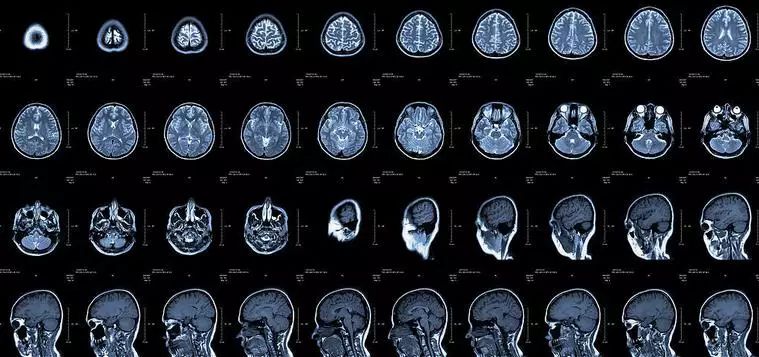

核磁共振(MRI):进入磁场,让体内氢原子核摇一摇,感受震动,评估检查结果

原理:利用收集磁共振现象所产生的信号而重建图像的成像技术,简单说就是相当于用手机摇一摇,让氢质子振动起来,再平静下来,感受一下里面的振动。

优点:与CT相比,它没有放射辐射,没有骨性伪影,能多方面、多参数成像,有高度的软组织分辨能力。

缺点:费用相对比较昂贵。

磁共振的远离简单的说:正常情况下人体内的氢原子核处于无规律的进动状态,当人体进入强大均匀的磁体空间内,在外加静磁场作用下原来杂乱无章的氢原子核一齐按外磁场方向排列并继续进动,当立即停止外加磁场磁力后,人体内的氢原子将在相同组织相同时间下回到原状态;这称为驰豫,而病理状态下的人体组织驰豫时间不同,通过计算机系统采集这些信号经数字重建技术转换成图像就可以给临床和研究提供科学的诊断结果。

磁共振和CT的区别主要在于成像的性质,CT是根据组织的密度,由于人体不同组织的密度不同,来发现病灶;而磁共振是判断不同加权所产生的不同信号。磁共振于对软组织滑膜、血管、神经、肌肉、肌腱、韧带、和透明软骨的分辨率高。由于其特殊的性质,磁共振看骨头不行,而在大脑的检查中则有着不可替代的作用。

在这里还要顺便提一下,磁共振扫描的时间相对CT会更长,但是并没有辐射,相对安全。还要说一句的是磁共振仪器是一个巨大的磁场,进去磁共振室一定要卸下随身携带的金属物品,不然都会被吸到机器上。曾今也有许多案例和教训,比如患者的输液架被紧紧吸住,所有人都拉不开,不得不叫来大型工程设备;还有患者要求将轮椅推入,医生拼命阻止,患者不理解,最后造成严重纠纷。